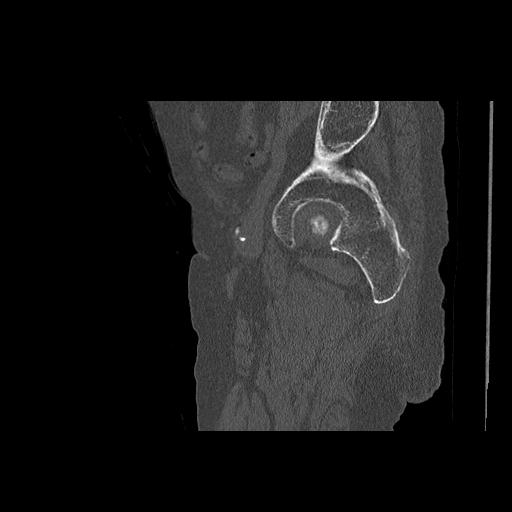

110286 2/17 股関節 2R 74歳女性 右人工骨頭